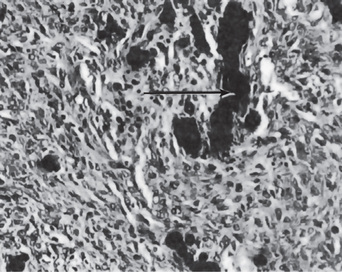

In the mouth, areas of dystrophic calcification may frequently be found in the gingiva, tongue or cheek. Such areas are also found in the benign fibromas of the mouth and adjacent structures (Fig. 15-2). One of the most common intraoral dystrophic calcifications is found in the pulp of teeth, and this has been discussed in Chapter 13 on Regressive Alterations of the Teeth. Boyle described the pulp calcifications as calcific degeneration of the pulp tissue. They are usually found in the teeth of older persons, although they also may be seen in young people. They may occur in the wall of blood vessels or in the perineural connective tissue of the pulp, or they may be rather diffusely scattered both in the pulp chamber and in the root canal. They appear as fine fibrillar calcifications which may coalesce to form large masses of calcific material.

Calcinosis is the presence of calcifications in or under the skin. There are two forms of calcinosis: calcinosis circumscripta, which, as the name suggests, is a circumscribed form, and calcinosis universalis, which is a generalized form. Calcinosis universalis is often associated with scleroderma and sometimes dermatomyositis. These different forms of calcinosis have been discussed by Johnson (Fig. 15-3).